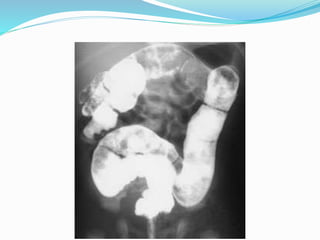

 Contrast Enema Is Diagnostic, And Also Therapeutic …

 Meconium Plug Syndrome

Meconium Plug Syndrome

 Mildest & Most Common Form Of Functional Distal

Obstruction In The Newborn.

 Obstruction Caused By Inspissated, Immobile

Meconium.

 Incidence 1 Case In 500 To 1,000 Neonates.1

 Etiology Is Unclear.

 Hint:  ContrastEnema Is Diagnostic, And Also Therapeutic …

Meconium Plug Syndrome Mildest & Most Common Form Of Functional Distal Obstruction In The Newborn.  Obstruction Caused By Inspissated, Immobile Meconium.  Incidence 1 Case In 500 To 1,000 Neonates.1  Etiology Is Unclear.